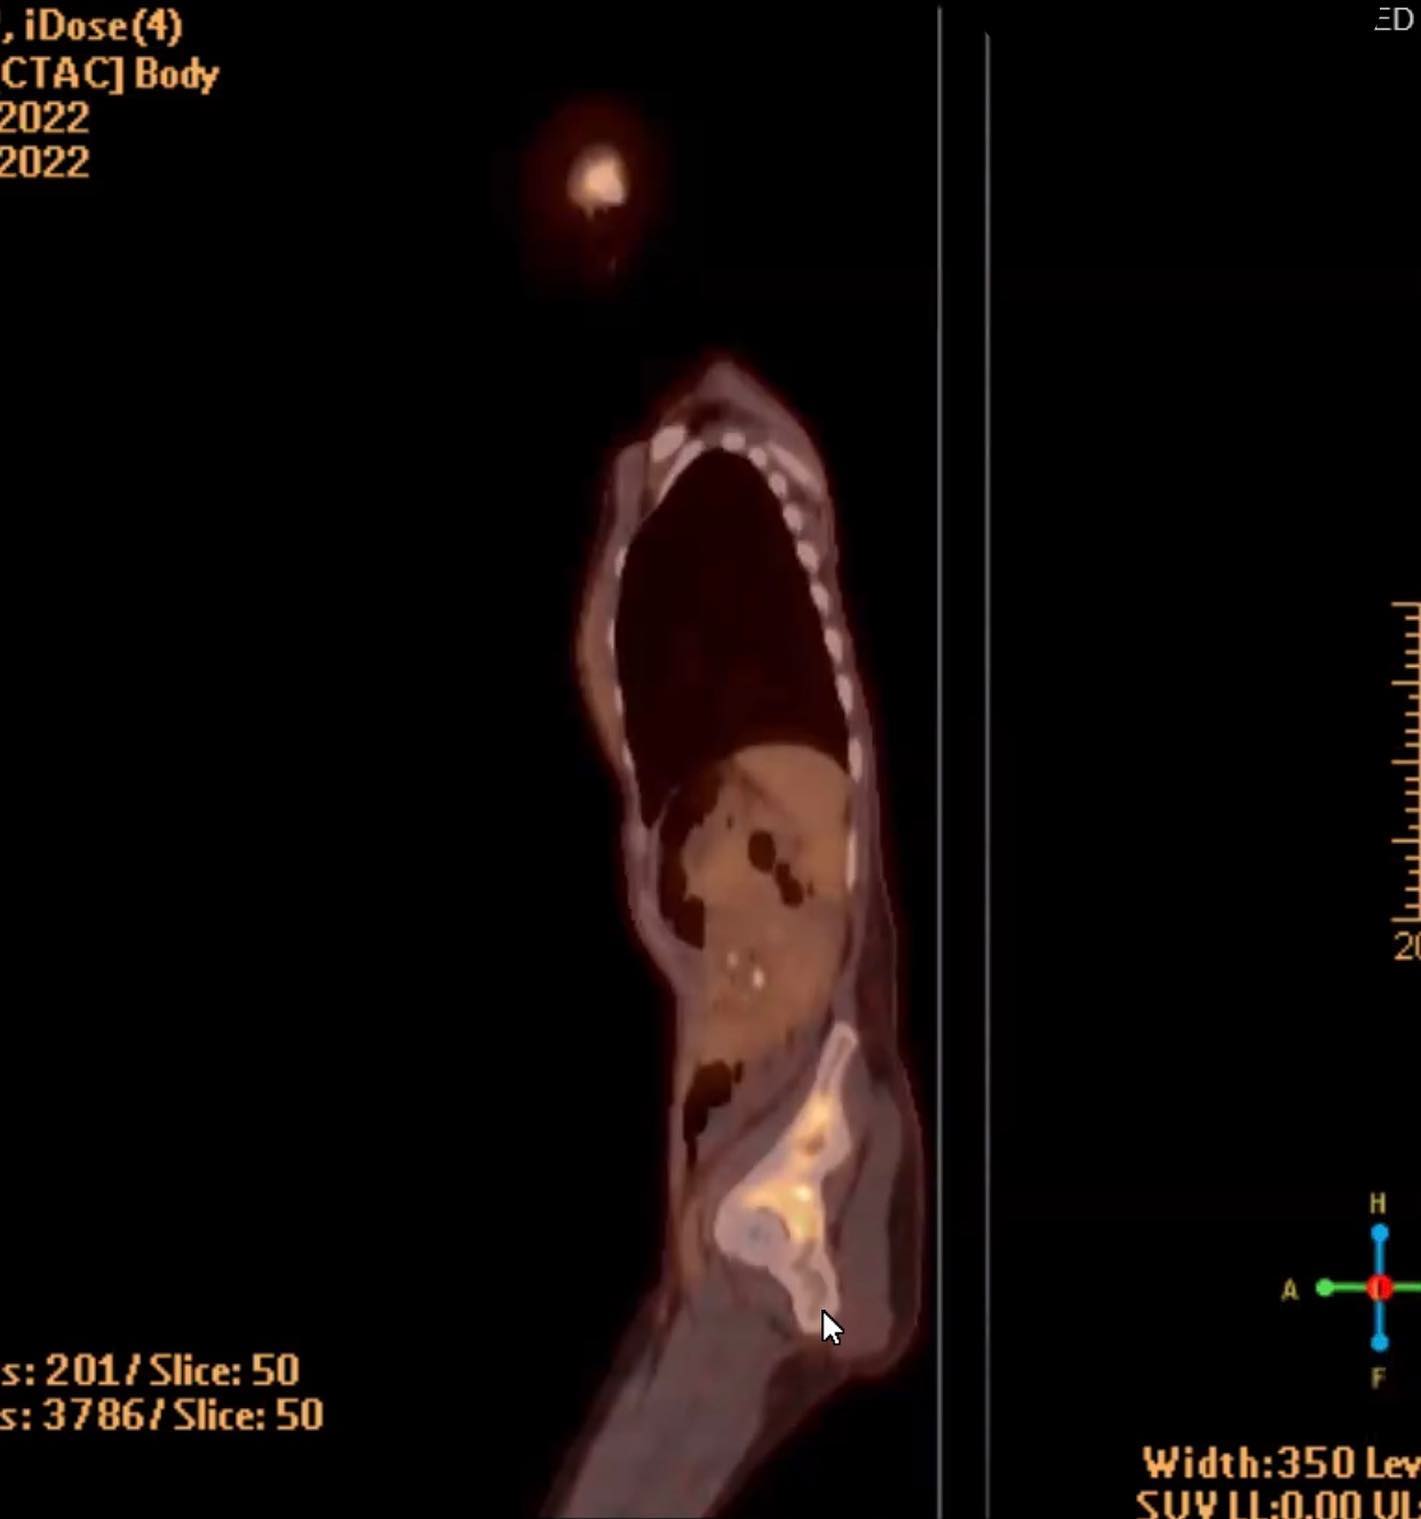

something big to share is that i’ve qualified for a trial. it’s being done all over the country and one base is santa rosa. it’s with a medicine called Trodelvy - (which is not the trial drug and that was the next one offered to me) and another one called magrolizumab. i have big and complicated and honestly just unreachable feelings about this. a couple doctors have told me i’ve got weeks left of my life. Other doctors say this could prolong my life with genuine quality. it could not work at all, like the others i tried. the disease progressed at a horrifying rate on the yew and keytruda. it could work in astonishing ways- like for people who i interact with on forums who have achieved “no evidence of disease” on trodelvy after trying many other courses of treatment. continued in comments…

i had another procedure this afternoon, drained another 850ml of fluid from around my lungs. this time went way better than the last; they went slower and didn’t puncture my lung like last time at the marin hospital. i felt calm and supported and feel some relief.

there is still a concerning amount of fluid build up around my liver, and there is excess fluid around my heart but not of great concern yet. i’m filling with rivers, i suppose.

my liver enzymes are very slowly going down which is encouraging. yet the tumours on my chest are growing and swelling and bleeding and it’s scary- though the wound care doctor said that they are neither infected nor necrotic, which is great.

i’ve had some good relief from pain and anxiety- and realized i was in so much pain when i checked myself in late saturday/early sunday that i didn’t even remember a lot that happened- i had a CT scan i didn’t know about.